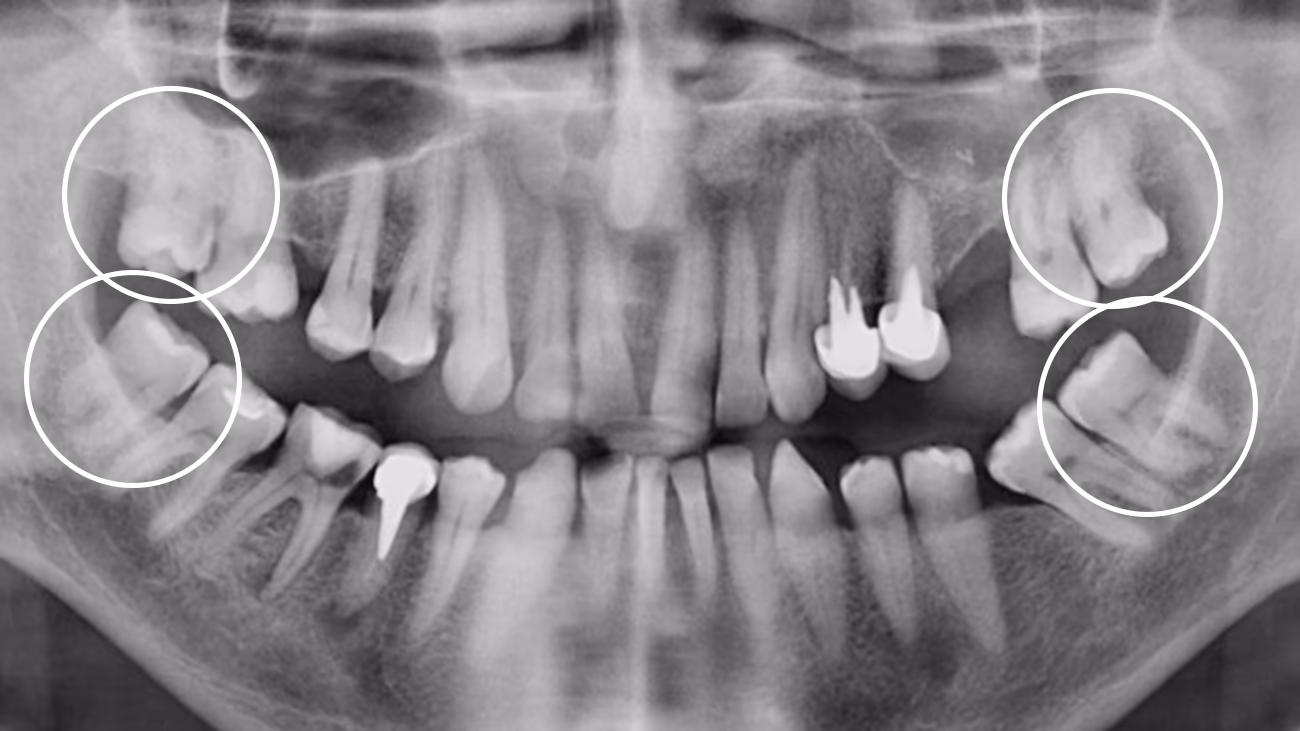

Так. КТ є обов’язковою для точного та безпечного видалення зуба мудрості.

3D-діагностика дозволяє визначити:

• положення зуба

• напрямок росту

• особливості коренів

• близькість до нижньощелепного нерва або верхньощелепної пазухи

У Sergatiy Dental Clinic КТ є обов’язковою перед видаленням зуба мудрості. Без КТ значно підвищуються ризики ускладнень.